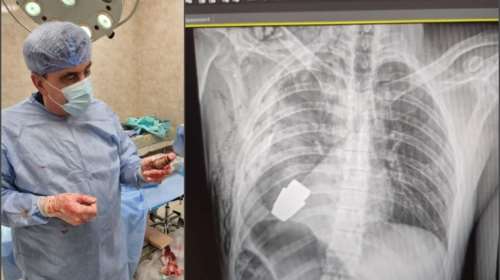

Ουκρανία: Χειροβομβίδα σφηνώθηκε στο στήθος στρατιώτη χωρίς να εκραγεί - Οι γιατροί κατάφεραν να την αφαιρέσουν

Ο 28χρονος στρατιώτης αναρρώνει μετά την επιτυχή επέμβαση αφαίρεσης χειροβομβίδας που είχε σφηνωθεί στο στήθος του.